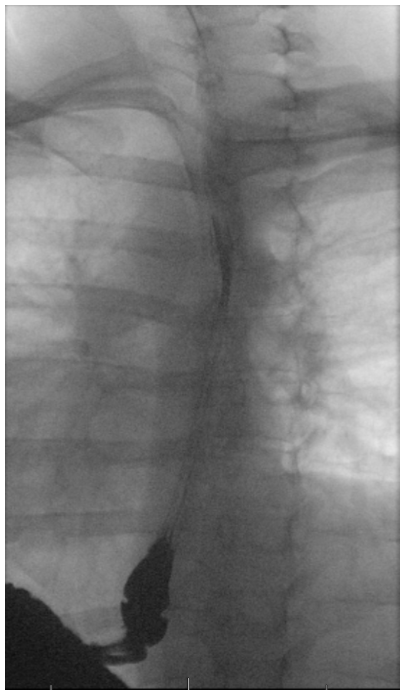

An esophagram is a video x-ray of the swallowing function in your esophagus, which is the tube that squeezes food and liquid from your throat to your stomach. If you have a problem in the function of your esophagus, you may have a variety of swallowing symptoms including feeling like food or pills stick in your chest and throat, chest pain during meals, regurgitation, and reflux.

If your doctor orders an esophagram, this will be done by a radiologist in the radiology department. You will drink a chalky contrast material called barium which lights up on x-ray. The doctor will film the barium traveling down your esophagus. The whole test is painless and noninvasive, and may last for 5-10 minutes. After the evaluation you will have a return appointment with your ENT doctor to discuss your test results.

| Example Esophagram X-rays | |